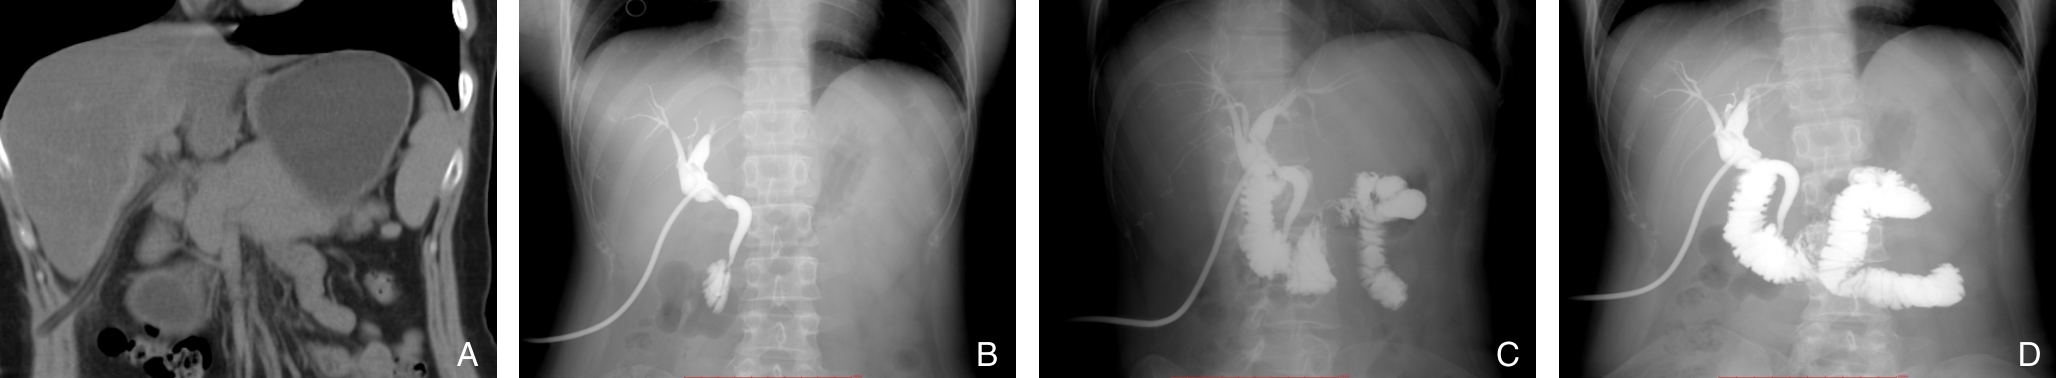

摘要:背景与目的 Hem-o-lok夹广泛应用于腹腔镜胆囊切除术(LC)中的胆囊管及血管闭合,但其术后移位虽罕见,却可进入胆总管形成异物,影像学表现易误诊为胆总管结石,增加诊断与治疗难度。针对该远期并发症的识别与处理,临床认知仍有不足。本文通过分析1例相关病例并结合文献复习,总结其临床特征及诊治要点。方法 回顾性分析中国人民解放军空军军医大学第二附属医院普通外科2025年10月收治的1例29岁女性患者的临床资料。患者4年前行LC,本次因体检发现“胆总管结石”1年余入院,术前影像学提示胆总管多发充盈缺损。患者拒绝内镜下逆行胰胆管造影治疗,遂行腹腔镜胆总管探查术(LCBDE),术中确诊为Hem-o-lok夹移位。分析其诊疗过程、影像学特征及术中所见,并结合文献进行讨论。结果 术前影像学提示胆总管多发结石。LCBDE术中经胆道镜探查,于胆总管中下段取出3枚移位的Hem-o-lok夹,周围未见胆色素结石,确诊为“胆总管异物(Hem-o-lok夹)”。术后置T管引流,恢复顺利出院。术后2个月T管窦道造影示胆总管通畅,无残留异物或结石,顺利拔管。结论 Hem-o-lok夹移位是LC术后一种罕见的远期并发症,影像学易误诊为胆总管结石。对有相关手术史的患者,应将其纳入鉴别诊断。LCBDE是确诊及处理该并发症的有效方式。规范术中操作及合理选择闭合方式,并加强术后随访,有助于降低此类并发症风险。